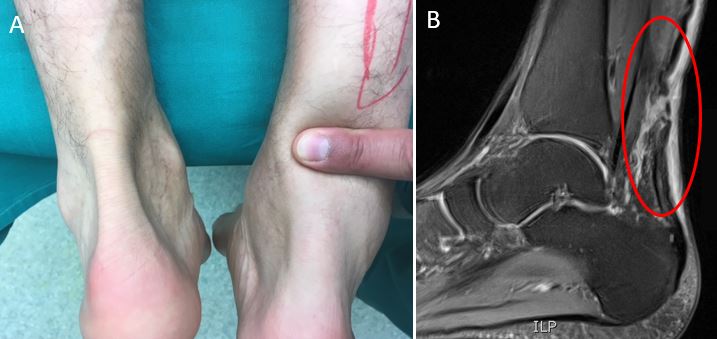

Στην ψηλάφηση υπάρχει κενό στο σημείο της ρήξης (επόμενη εικόνα αριστερά). Υπάρχουν κλινικά τεστ που οριστικοποιούν τη διάγνωση, καθιστώντας τη διενέργεια απεικονιστικών εξετάσεων πολλές φορές περιττή (Thompson test, Matles test). Παρόλα αυτά, σε αμφίβολες περιπτώσεις, η διάγνωση μπορεί να επιβεβαιωθεί με τη μαγνητική τομογραφία (επόμενη εικόνα δεξιά) και το υπερηχογράφημα.

Ρήξη αχιλλείου τένοντα: A. Χαρακτηρηστική εικόνα ψηλαφητού κενού, Β. Εικόνα στη μαγνητική τομογραφία